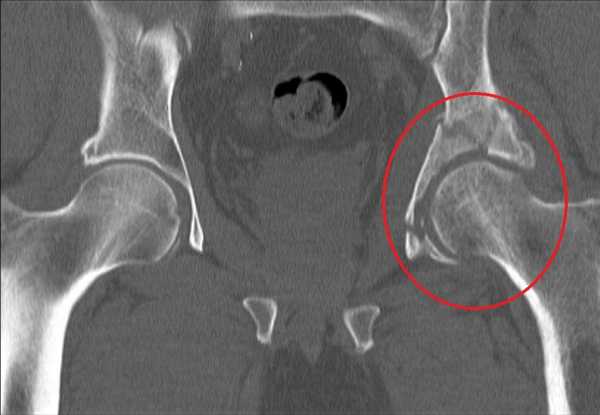

Снимок компьютерной томографии перелома таза в области вертлужной впадиныДля того чтобы быть полностью уверенным в диагнозе, врач также назначает пройти диагностирование на компьютерной томографии. Благодаря такому методу диагностирования можно точно обнаружить смещение или присутствие оскольчатого перелома. Для определения открытого перелома проводится ректальное и вагинальное обследование.

Компьютерная томография таза

Данные исследования позволяют установить какой именно участок вертлужной впадины был разрушен, есть ли смещение костей. С целью оценить неврологическую составляющую для консультации приглашается невропатолог. На основе собранных данных врач формирует диагноз и определяет тип перелома.

Ставят диагноз основываясь на симптомах, данных рентгенологического и КТ исследований. Рентген делают в нескольких проекциях, снимок в прямой проекции оказывается малоинформативным для установления характера полученных повреждений.

КТ проводят для постановки более точного, правильного диагноза. Она позволяет определить наличие или отсутствие смещения костных фрагментов. Ректальным и вагинальным методами исследования определяют характер перелома, он может быть открытым или закрытым.